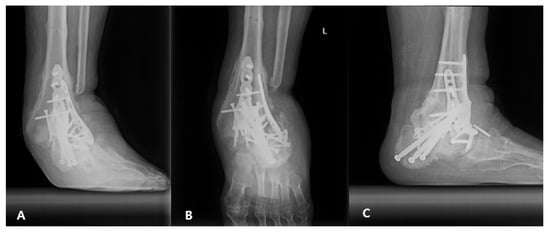

2.2. Surgical Procedure

2.3. Postoperative Care